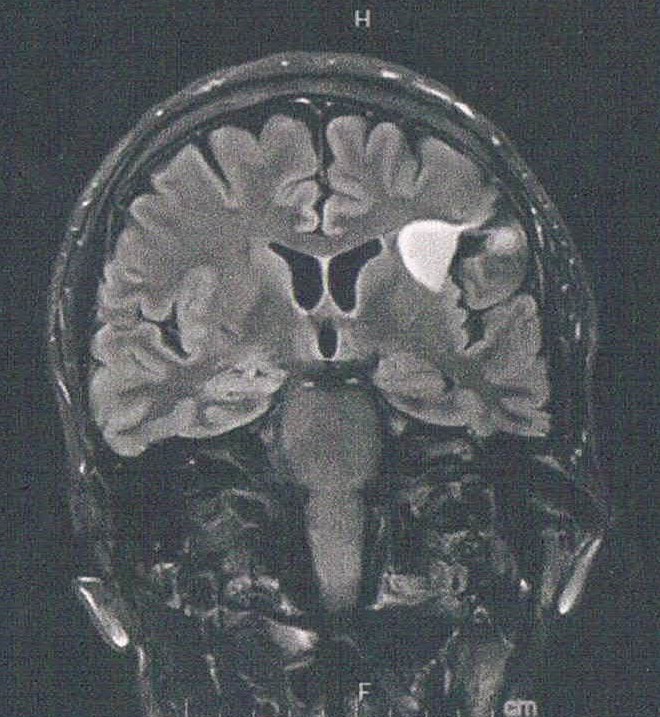

- びまん性星細胞腫グレード2(悪性転化しやすい腫瘍)

- MRIが新しくなっていた。3T

- 1年に1〜2mmほどおおきくなっている

- てんかん、言語障害に注意、5年以内くらいに再手術か?

- 下方向に大きくなると取りにくくなるので、そうなる前に手術